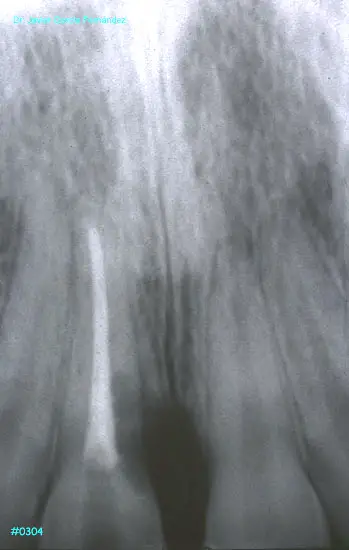

image348